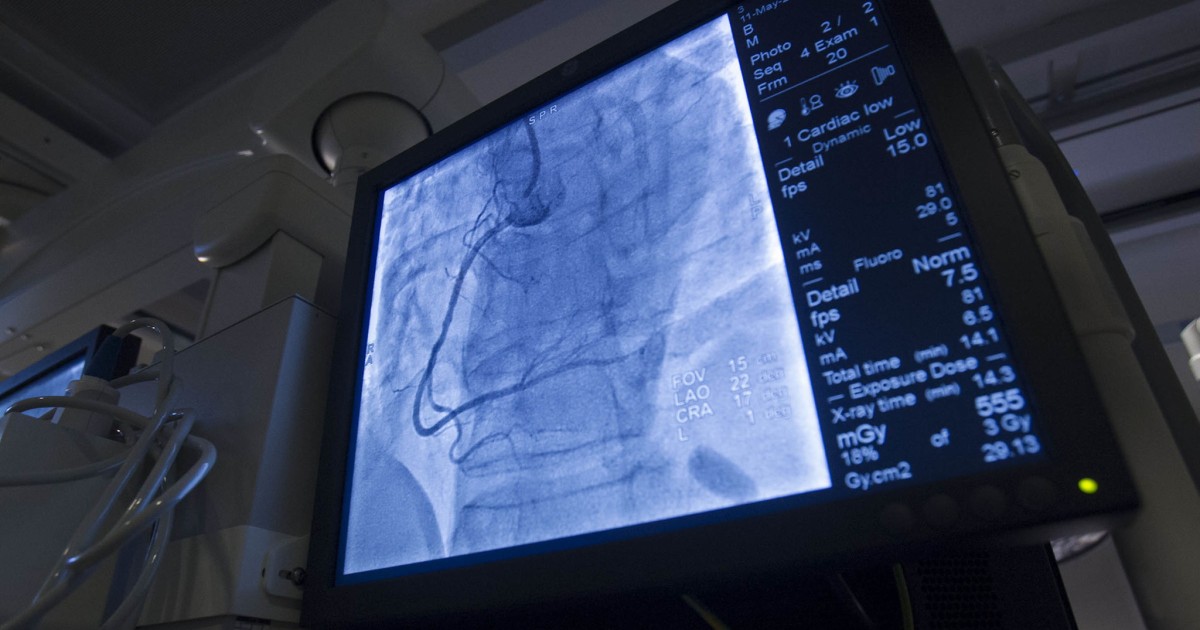

When diet changes and medications are not effective at treating renal artery stenosis, a procedure called renal angioplasty and stenting may be recommended. This surgical procedure lowers blood pressure, increases blood flow to the kidneys, and prevents further complications such as organ damage. Renal angioplasty and stent placement involve the use of a long flexible tube called a catheter, a small balloon, and a stent or mesh wire tube. A small incision is made in the patient's thigh, and the surgeon guides the catheter from the femoral artery to the affected renal artery. A small balloon at the end of the catheter is then inflated, and the plaque or excess tissue are pushed against the walls of the artery. This mechanism effectively widens the artery. The surgeon then places the wire mesh tube or stent inside of the widened artery to hold its expanded position. The balloon is then deflated, and the catheter and balloon are removed. The stent stays in place permanently to allow for better blood flow to the kidneys. Renal angioplasty and stenting placement is a minimally invasive procedure, and it has a significantly quicker recovery time than other traditional open surgical procedures.